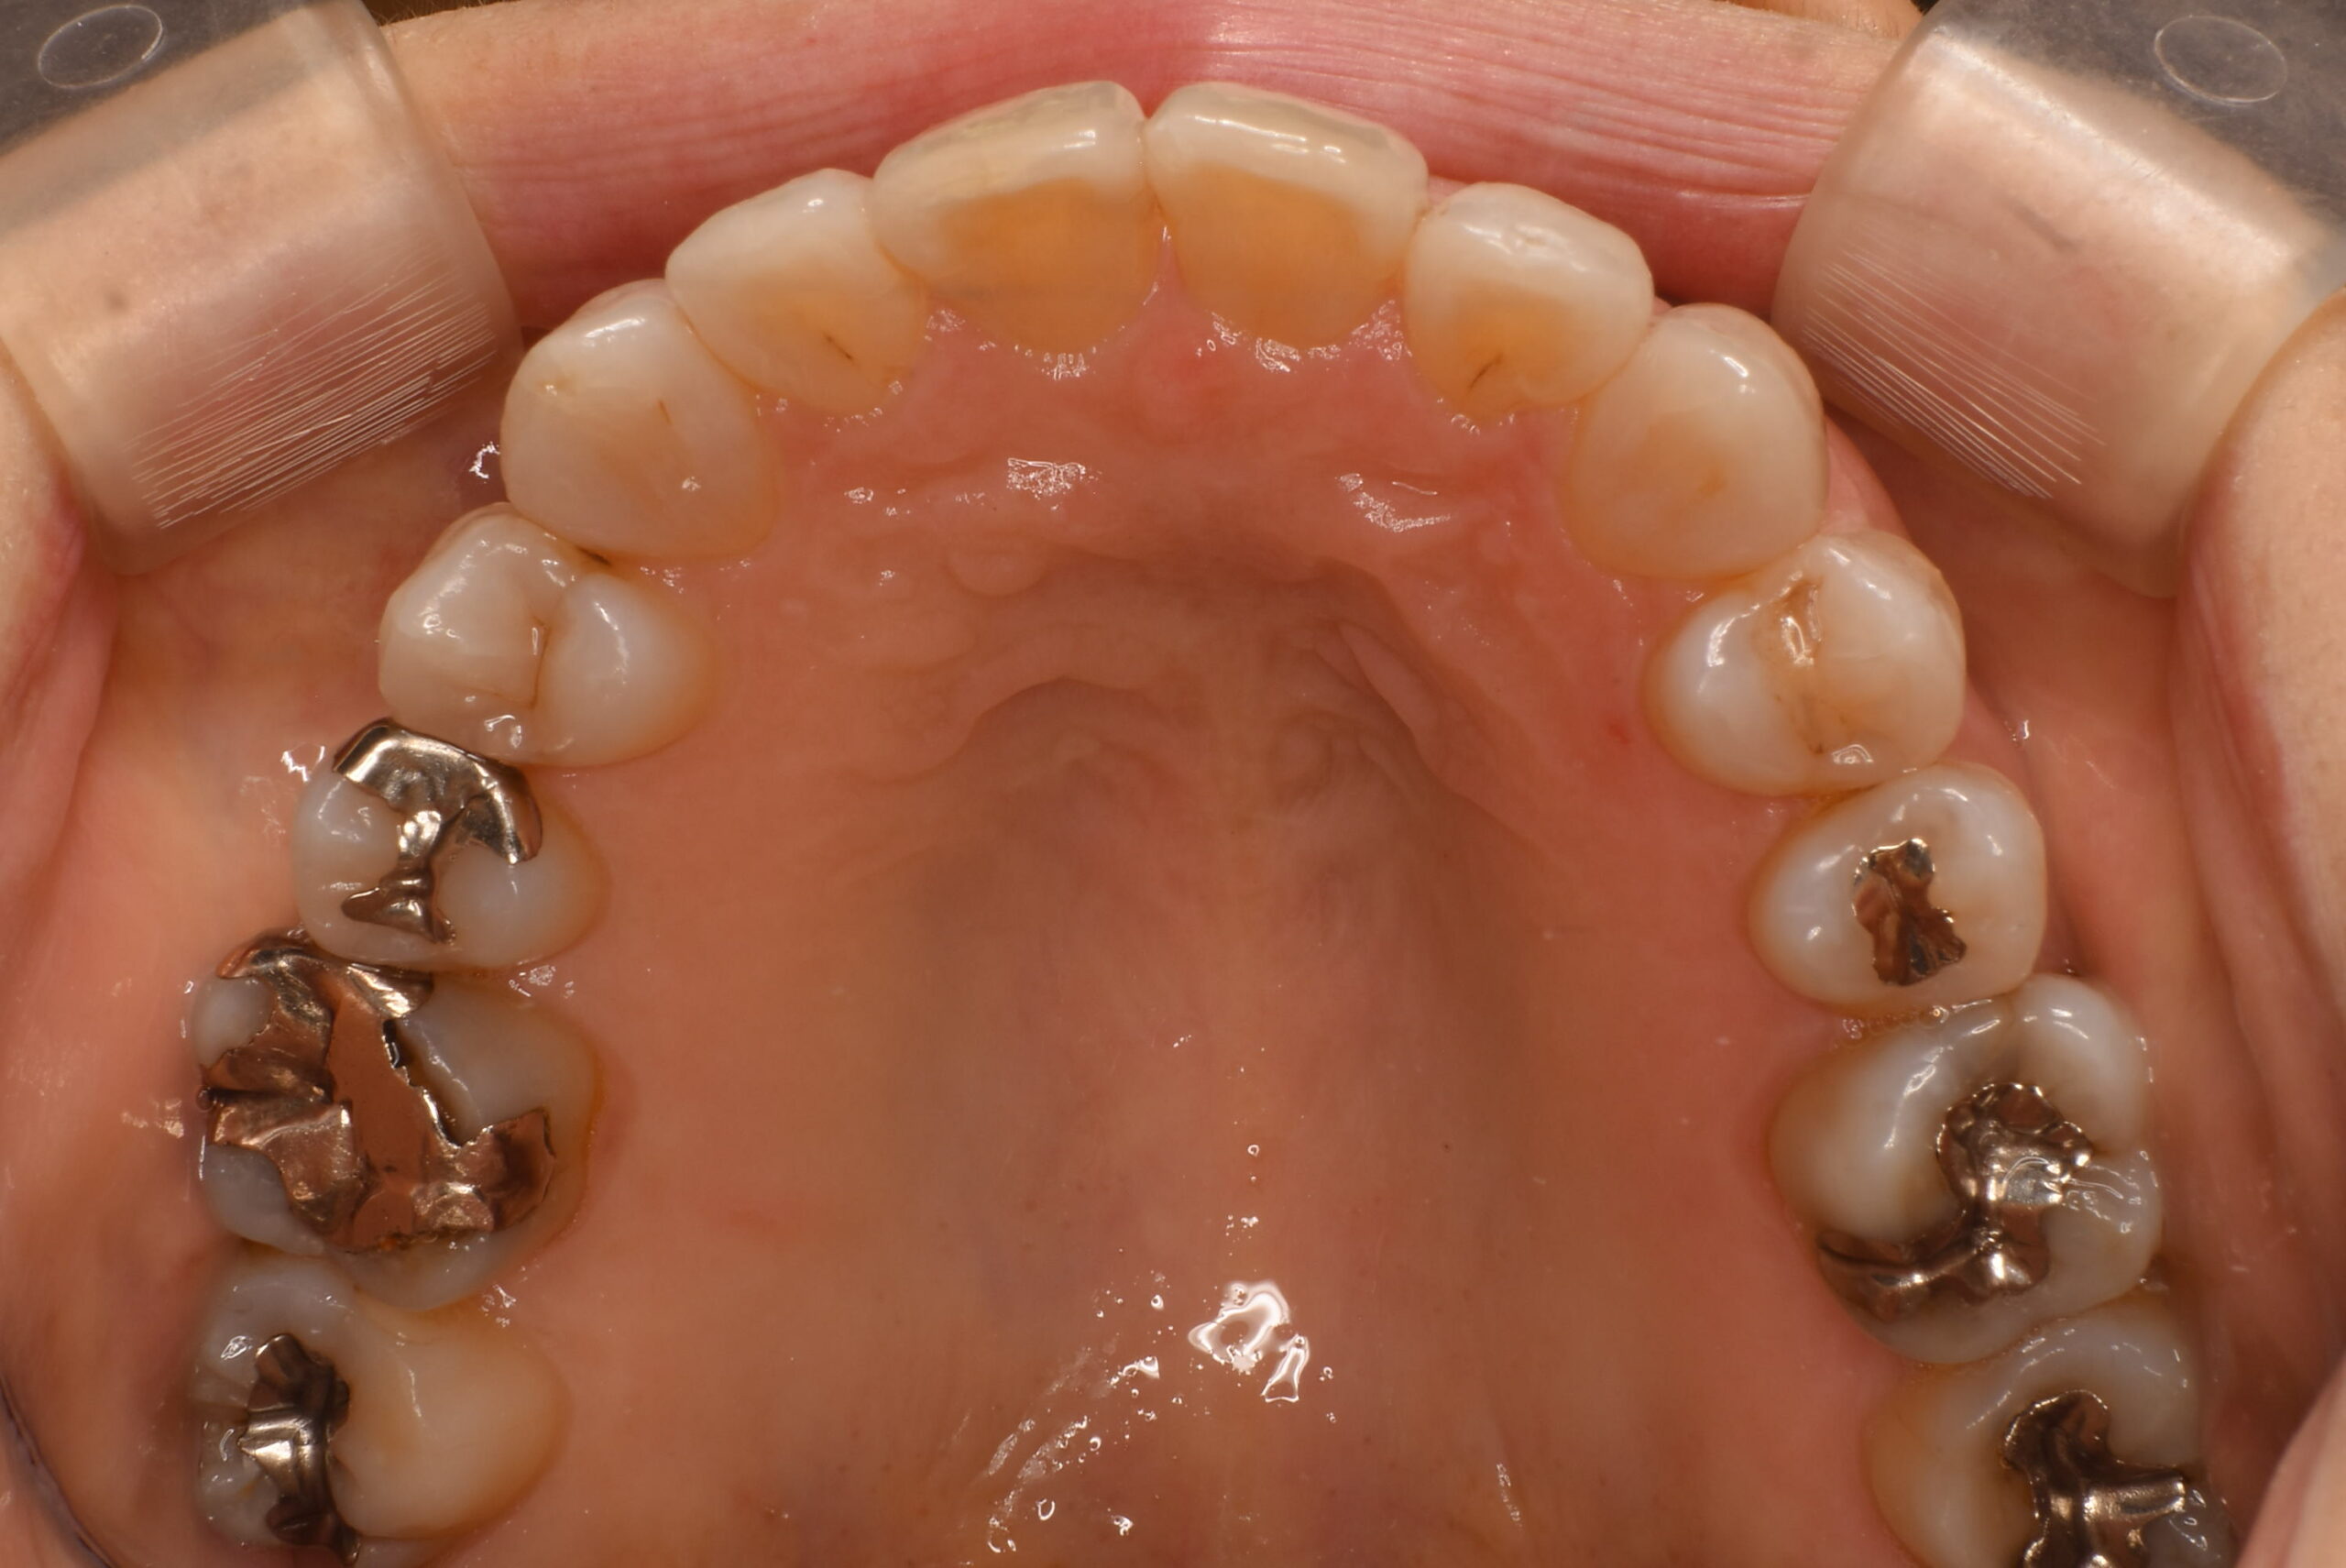

- AFTER

上顎咬合面_治療後

| 治療内容 | 患者様は、不揃いな歯並びと噛み合わせの違和感、加えて将来的な口腔内の病気への不安を訴えて来院された。また、慢性的な肩こりや首の痛みもあり、これらが歯並びや咬合との関連についても心配されていた。 インビザラインによるマウスピース型矯正を選択。アライナーを用いて歯列全体を整列し、叢生の改善とともに前歯部の位置と角度を理想的な状態に調整。必要に応じて歯と歯の間のわずかな削合を行い、歯を並べるスペースを確保した。 |

| 治療期間/通院回数 | 24ヶ月 |